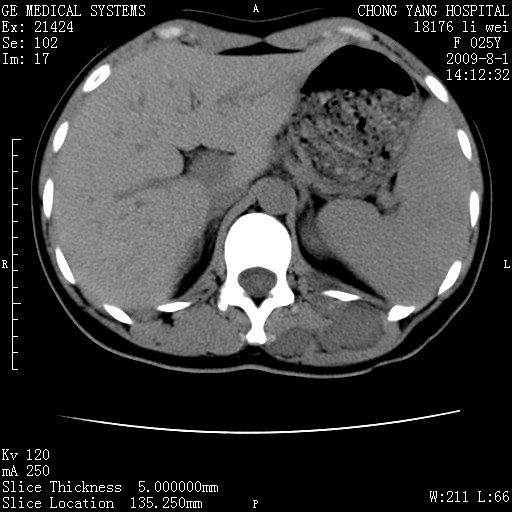

以下是引用pujunzhi在2009-8-1 20:23:00的发言:[br]胸椎旁及背部肌间良性病变,范围广,边界清,沿肌间生长,考虑淋巴管瘤、血管瘤,建议增强扫描。